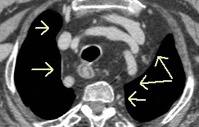

Raro. (2-9% de los T. tímicos). Asintomático. Contiene grasa (hasta 90%) y tejido timico (10-33%). Pueden ser muy grandes y confundirse con cardiomegalia. La tomografía “clásica” muestra los límites de la silueta cardiaca. (flechas)

Líneas paraespinales formando un “paréntesis” por encima del diafragma. El signo señala el origen “intratorácico” de la lesión.

Conrad A et al. Pott’s disease associated with large and multiple abscesses in a 30-year-old migrant from Chad. BMJ Case Rep 2018

(lesiones toracoabdominales) La divergencia de las líneas paraespinales apunta a lesión toracoabdominal, que desde el tórax desciende y penetra en el abdomen.

Signo del “iceberg” positivo en Tb vertebral

Afectación por vía hematógena. Región dorsolumbar más frecuente. Afectación inicial: irregularidad de los platillos vertebrales, disminución del disco intervertebral con esclerosis ósea adyacente. Kim. Radiographics.2001